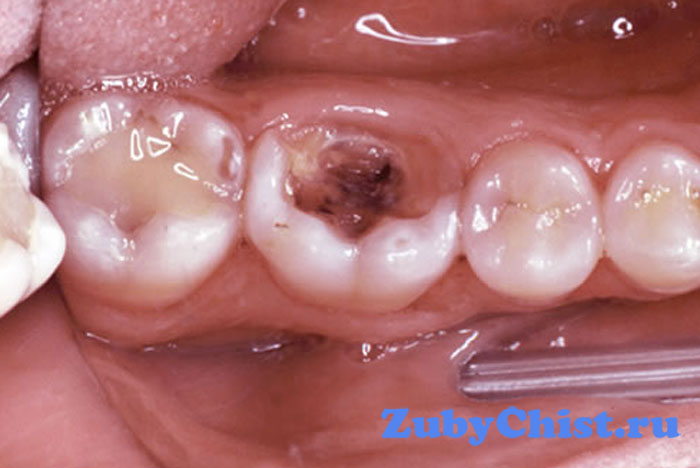

Пульпит молочного зуба по своей природе является сильным воспалением твердых тканей внутри и снаружи кости. Обычно пульпит развивается как осложнение запущенного кариеса. В некоторых случаях заболевание развивается и самостоятельно, но такое бывает только после серьезной челюстно-лицевой травмы. Воспаление развивается по разным путям – хроническому или острому. Но сегодня нас интересует как это заболевание переносит молочный зуб и как проводить лечение.

Пульпит временных зубов развивается достаточно часто, обычно в возрасте около 2 лет. Болезнь коренных зубов, которые растут ближе к горлу, появляется в возрасте – от 3 лет и до момента их смены на постоянные.

Теперь рассмотрим, как выглядит классификация пульпитов у детей:

- Острый. Он также делиться на гнойный и серозный, который затягивает в воспаление также и лимфатические узлы;

- Хронический. Подразделяется на фиброзный, гипертрофический и гангренозный;

- Обострение патологии в хронической форме.